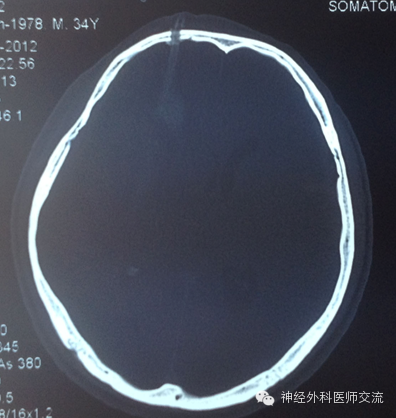

②行CT检查,动态观察血肿的变化,血肿基本消失(清除80%以上),可拔管,缝合局部头皮,3~5 d拆线。

C 低颅压——过度、过快抽吸、引流出血或脑脊液所致。

D 气脑——原因多为操作时一过性低颅压,致气体进入颅内。